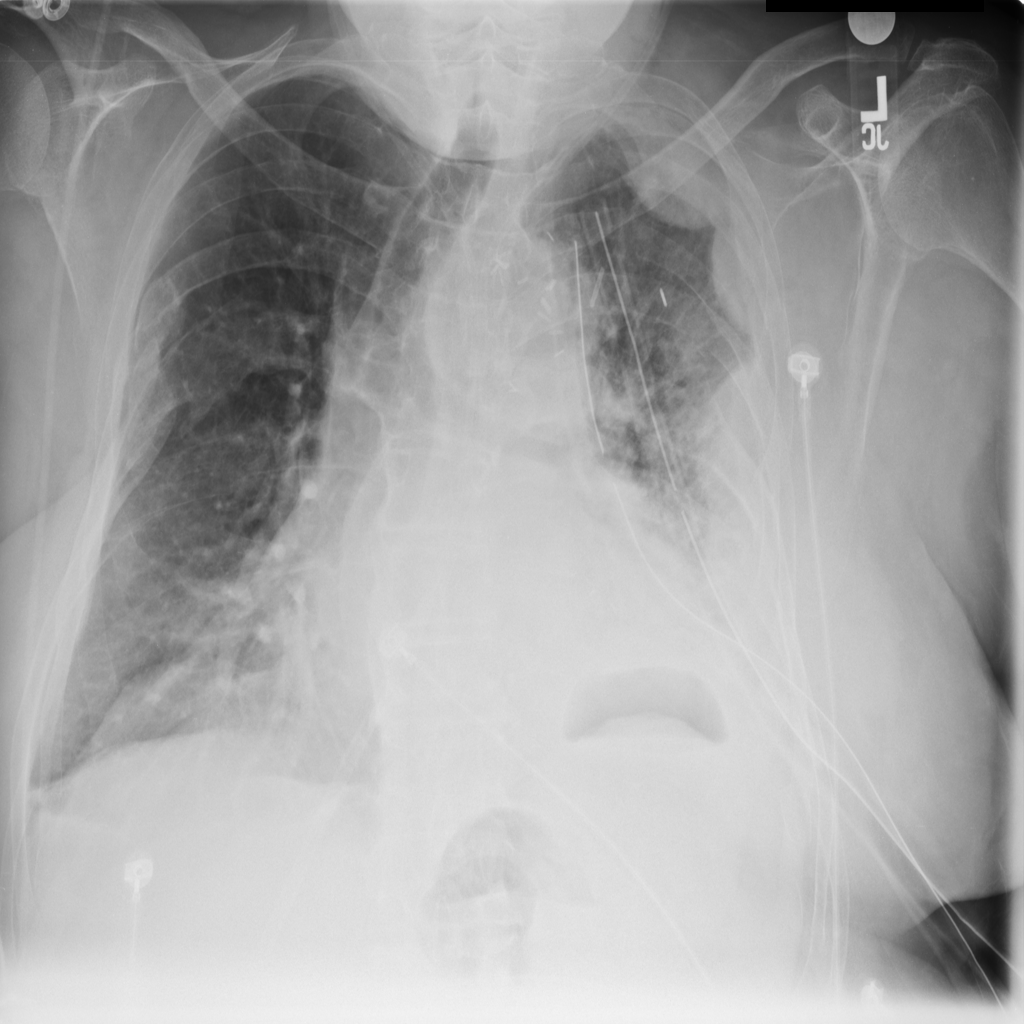

PAT-50E5 · IMG-008Mass

PAT-50E5 · IMG-008

PA